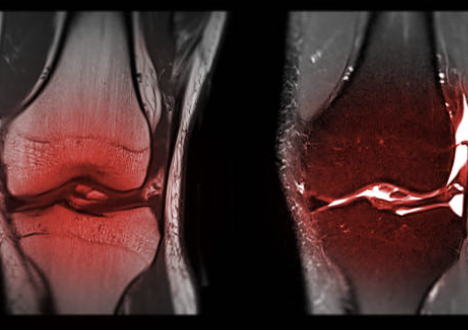

무릎 십자인대 파열 증상 및 십자인대 파열에 대해 알아보는 시간 갖도록 하겠습니다.

십자인대는 무릎 관절 내부에 있는 4개의 인대 중 하나로, 대퇴골과 승골 사이에 위치해 있습니다. 십자인대는 무릎 관절의 안정성을 유지하는 역할을 담당합니다. 무릎 관절에 직접적인 충격이 가해지거나, 무릎이 강한 스트레스를 받았을 때 십자인대가 손상되는 경우가 있습니다. 이러한 십자인대 손상은 스포츠 활동이나 사고 등으로 발생할 수 있습니다. 십자인대 손상 증상으로는 무릎 통증, 부종, 불안정감 등이 있으며, 심한 손상의 경우 수술이 필요할 수도 있습니다. 십자인대 손상을 예방하기 위해서는 적절한 스포츠화를 착용하고, 몸을 충분히 기르며, 스포츠를 할 때 안전장비를 착용하는 것이 중요합니다.

무릎 십자인대 파열은 무릎 관절 내부에 있는 십자인대 중 하나가 부분적으로 또는 완전히 파열되는 상황을 말합니다. 무릎 십자인대 파열 증상은 다양합니다. 주요 증상은 다음과 같습니다.